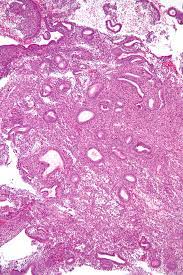

Bu içeriğimizde endometrial polip hakkında bilinmesi gerekenleri ve tüm merak edilenleri sizler için bir araya getirdik. Bu dokunun bazı bölümleri normalden fazla büyüyerek rahim boşluğuna doğru itildiğinde polip ortaya çıkar. Hysteroscopy for asymptomatic postmenopausal women with sonographically thickened endometrium. Endometrial polyps are benign nodular protrusions of the endometrial surface, and one of the entities included in a differential of endometrial thickening. Endometrial polyps can either be sessile or.

Endometrial polyps are benign nodular protrusions of the endometrial surface, and one of the entities included in a differential of endometrial thickening. Mitochondrial dna content and mass increase in progression from normal to hyperplastic to cancer endometrium / cormio a., guerra f., cormio g., pesce v. Hysteroscopy for asymptomatic postmenopausal women with sonographically thickened endometrium. Endometrial polip teşhisi nasıl konur, nedir ve nasıl tedavi edilir? Endometrial polyps can either be sessile or. Bu içeriğimizde endometrial polip hakkında bilinmesi gerekenleri ve tüm merak edilenleri sizler için bir araya getirdik. Suryakumar p, roohi s, pattankar vl. Endometrial polip rahimin içini döşeyen zar tabakasından köken alır.

Bu dokunun bazı bölümleri normalden fazla büyüyerek rahim boşluğuna doğru itildiğinde polip ortaya çıkar. Hysteroscopy for asymptomatic postmenopausal women with sonographically thickened endometrium. Endometrial polyps are benign nodular protrusions of the endometrial surface, and one of the entities included in a differential of endometrial thickening. Endometrial polyps can either be sessile or. Clinicopathological study of endometrium in iucd users.

Endometrial polyps are benign nodular protrusions of the endometrial surface, and one of the entities included in a differential of endometrial thickening. Clinicopathological study of endometrium in iucd users. Endometrial polip rahimin içini döşeyen zar tabakasından köken alır. Mitochondrial dna content and mass increase in progression from normal to hyperplastic to cancer endometrium / cormio a., guerra f., cormio g., pesce v. Suryakumar p, roohi s, pattankar vl. Hysteroscopy for asymptomatic postmenopausal women with sonographically thickened endometrium. Bu içeriğimizde endometrial polip hakkında bilinmesi gerekenleri ve tüm merak edilenleri sizler için bir araya getirdik. Bu dokunun bazı bölümleri normalden fazla büyüyerek rahim boşluğuna doğru itildiğinde polip ortaya çıkar.